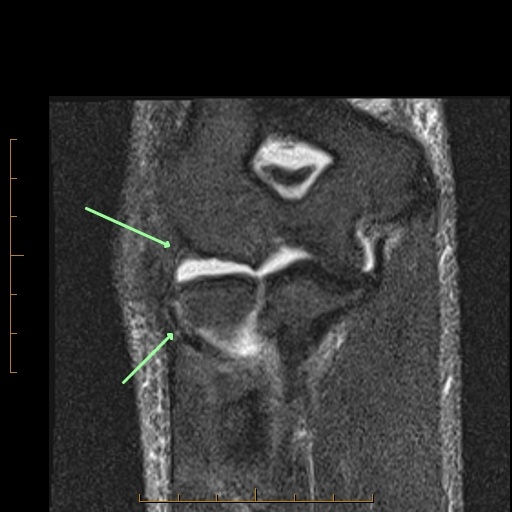

- Lateral capsule (torn-arrow, images two and three)

- Proper radial collateral ligament (torn-arrow, images two and three).